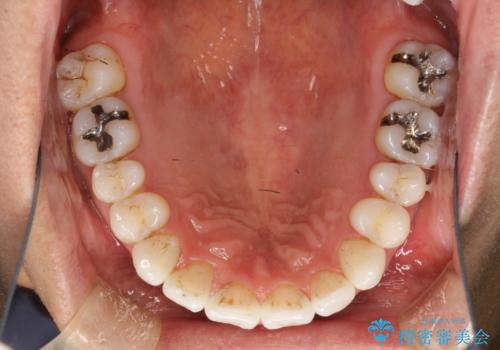

インビザライン終了時のPMTC

- インビザライン治療が終了し、アタッチメント除去の際にクリーニング(PMTC)も希望されました。

PMTC60分1万円+tax(保険適応外)を行いました。

インビザライン矯正治療は、歯にアタッチメント(歯を動かすための突起物)をつけます。そのため、矯正治療が終了し、アタッチメントを外すと着色が目立つことがあります。矯正治療の終了のタイミングではクリーニングを行い、着色の除去や歯と歯の間・歯と歯肉との境目などのケアをしっかりすることをおすすめしています。